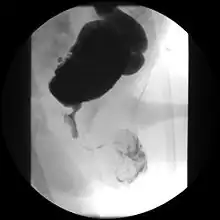

| A paraplegic patient with neurogenic bladder on regular ultrasound follow-up showing thickened bladder wall with trabeculations and sediments within the bladder. | |

Ultrasound imaging can give information on the shape of the bladder, post-void residual volume, and evidence of kidney damage such as kidney size, thickness or ureteral dilation.[9] Trabeculated bladder on ultrasound indicates high risk of developing urinary tract abnormalities such as hydronephrosis and stones.[10] A voiding cystourethrography study uses contrast dye to obtain images of the bladder both when it is full and after urination which can show changes in bladder shape consistent with neurogenic bladder.[9]